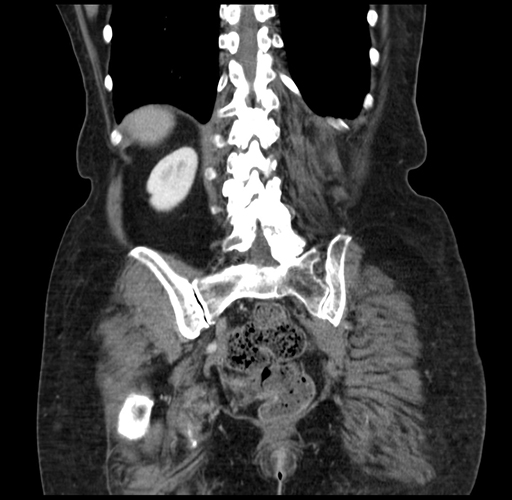

Coronal Venous